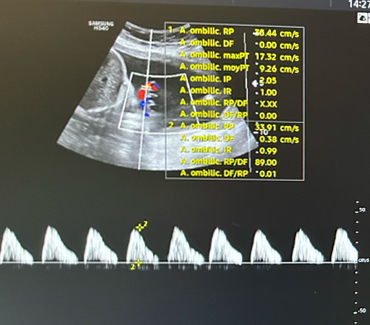

Il existe une franche cassure de la courbe, le fœtus est passé au troisième percentile. L’échographie en figure 1 est un écho-Doppler de l’artère ombilicale. Elle montre une diastole ombilicale nulle. Il s’agit donc d’un RCIU et non d’un fœtus petit pour l’âge gestationnel.

Concernant l’échographie de vitalité fœtale (figure 3), elle décrit :

– l’analyse du Doppler de l’artère ombilicale qui témoigne des échanges entre le fœtus et la mère (par ordre de gravité : diastole ombilicale positive normale ; diastole ombilicale nulle ; reverse-flow) ;

– l’analyse du Doppler de l’artère cérébrale moyenne qui peut mettre en évidence une redistribution cérébro-placentaire ou une anémie fœtale.